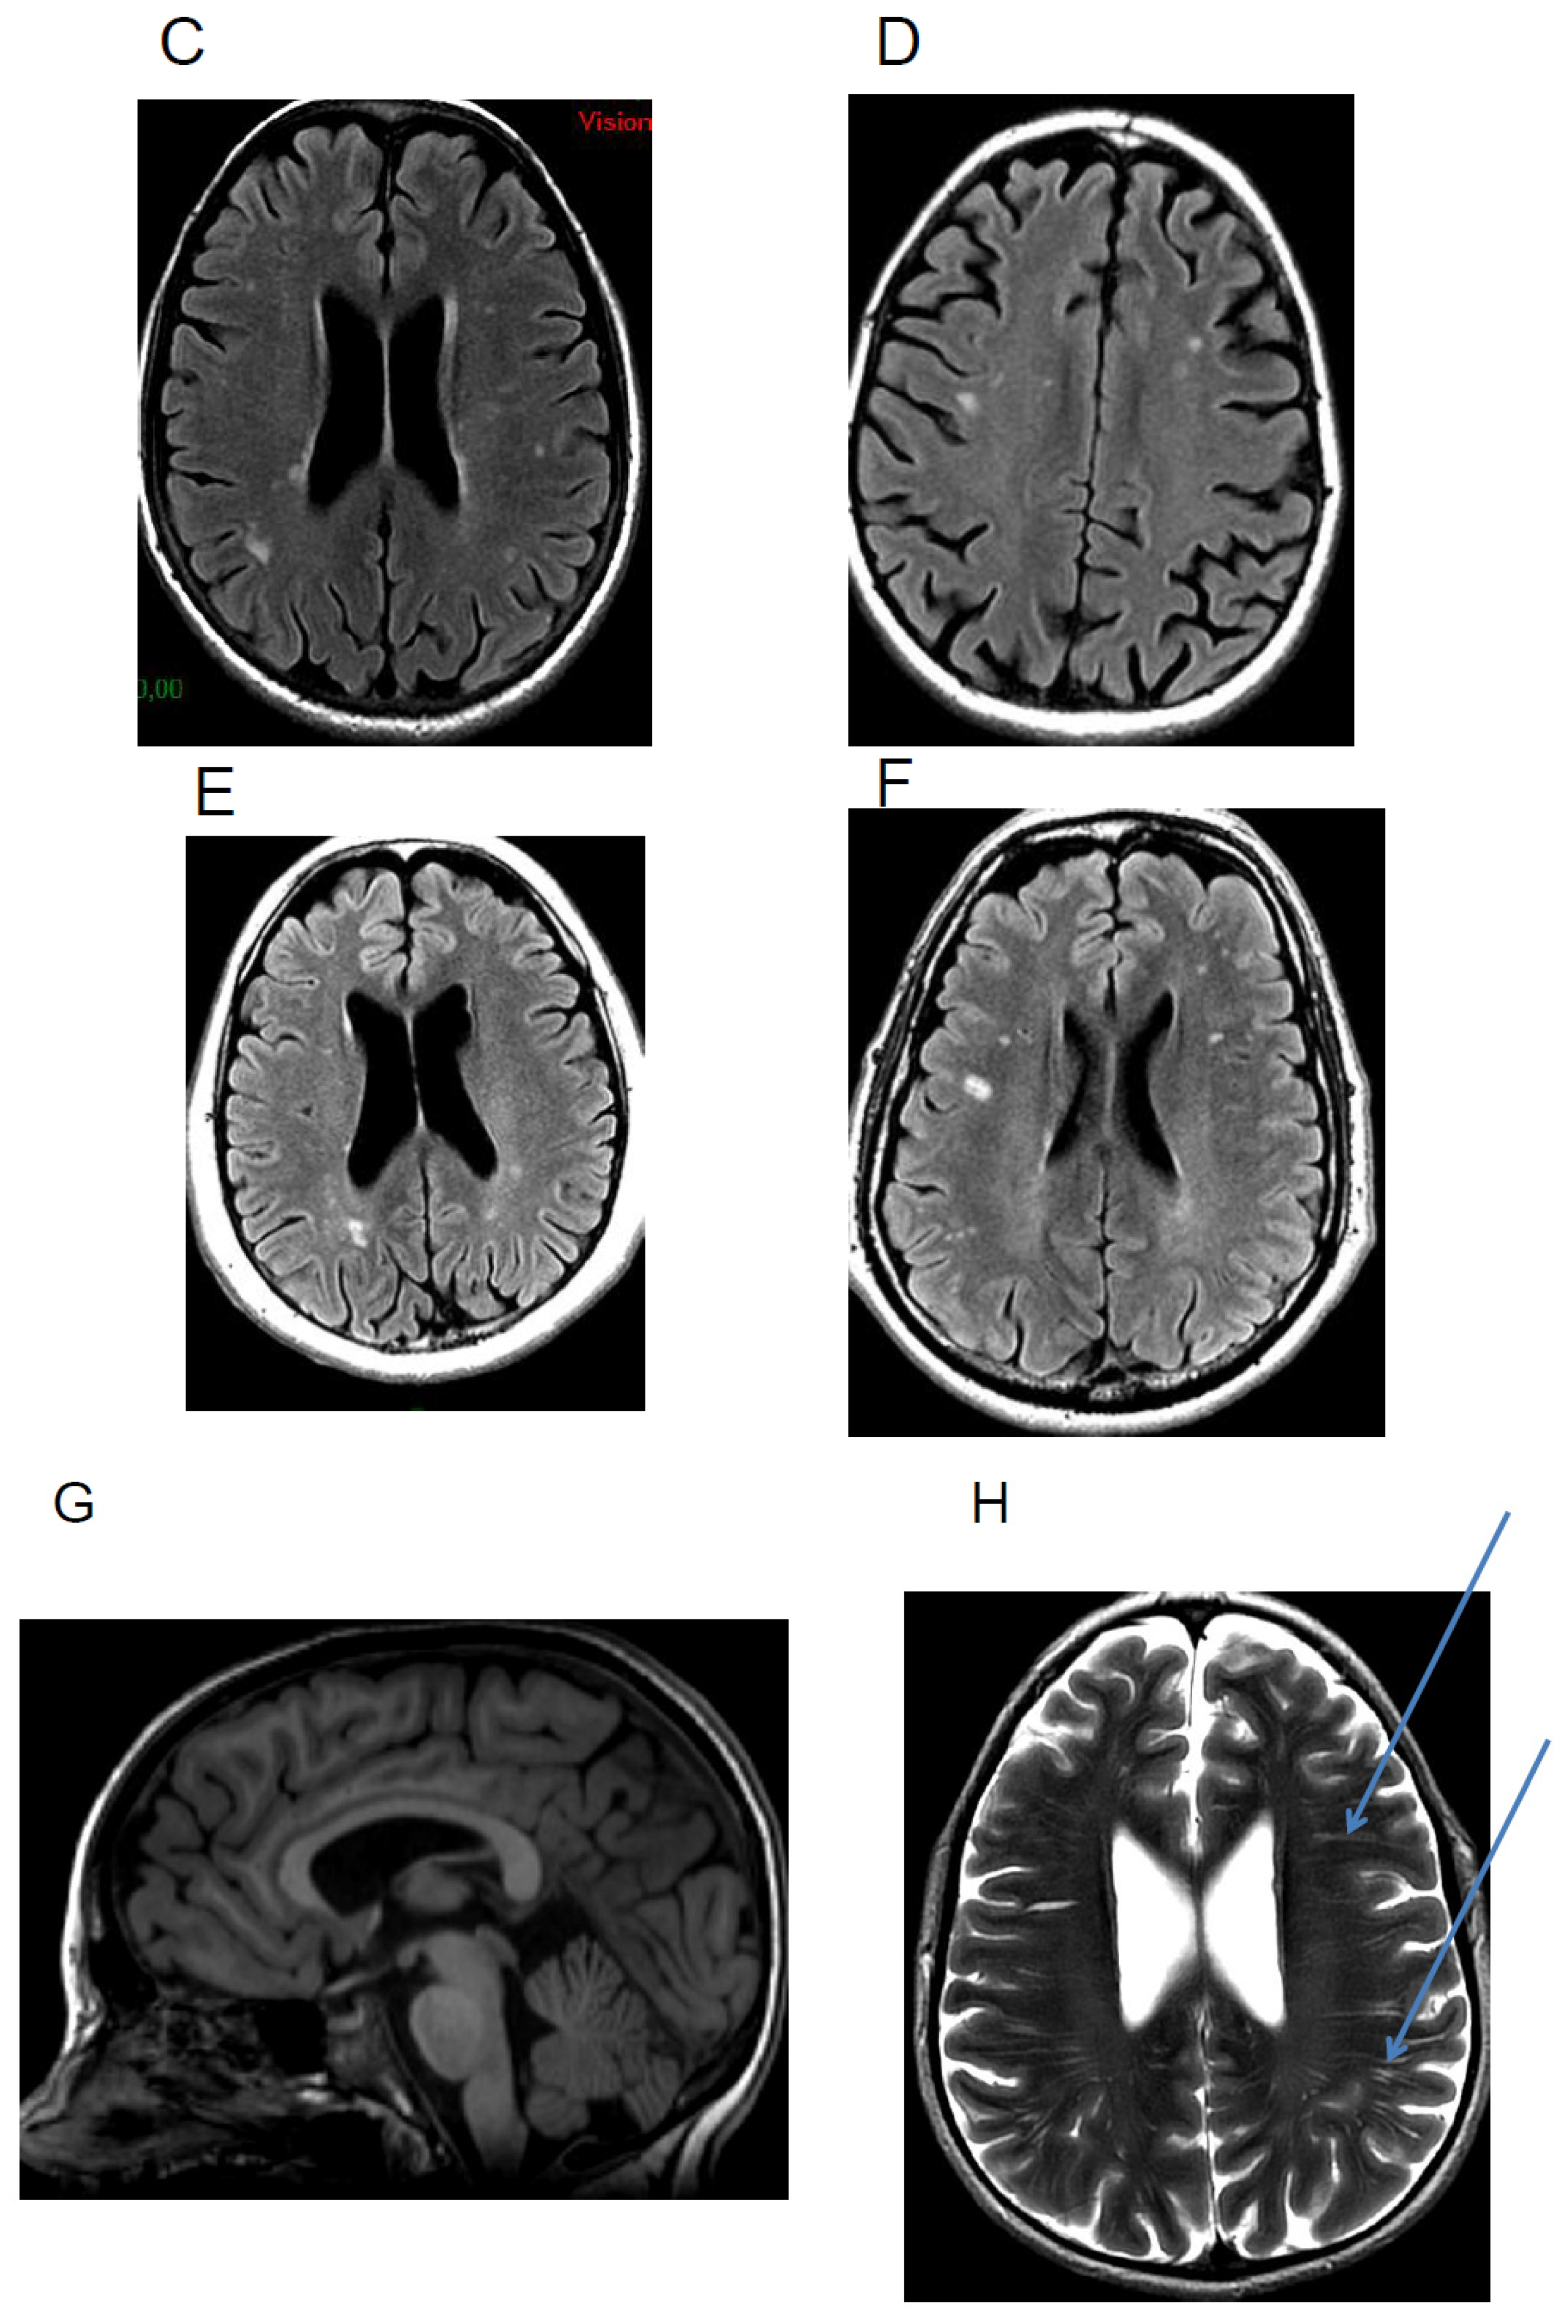

5.2. Cortical Atrophy

6.1. Grey Matter